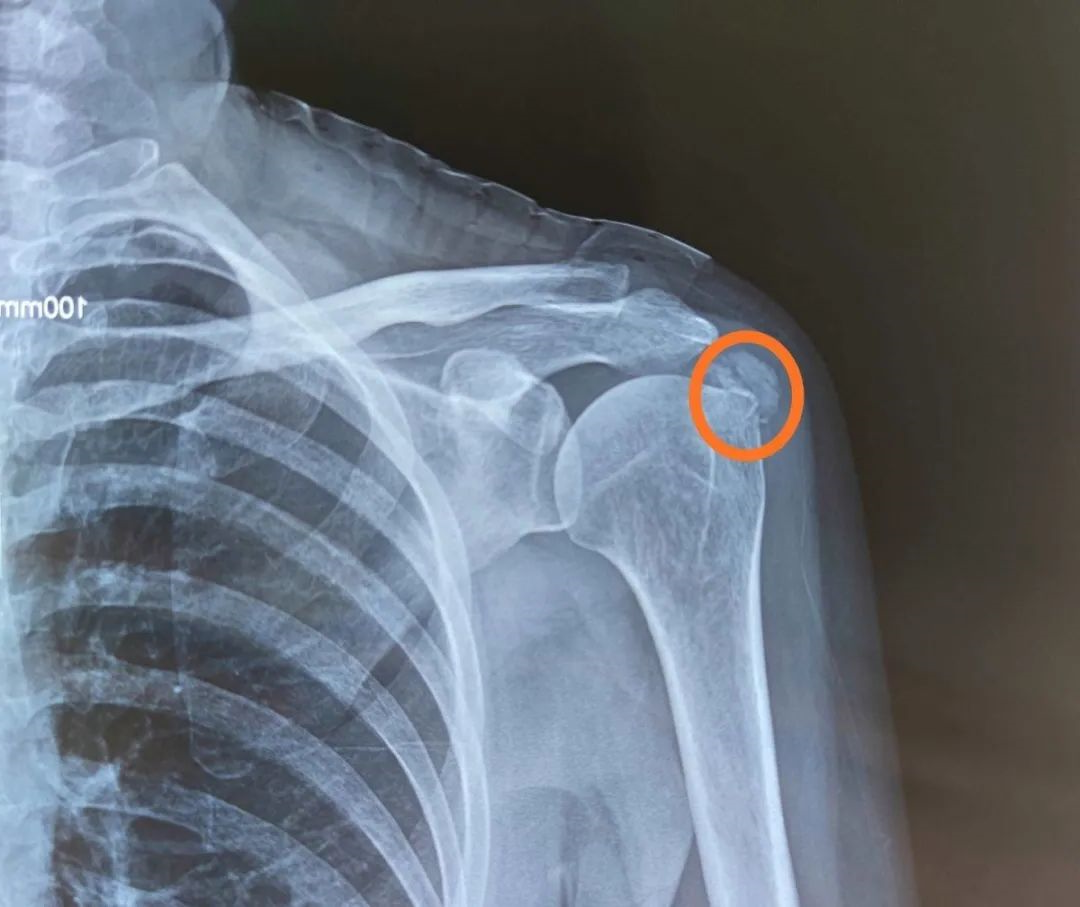

钙化性肌腱炎

钙化性肌腱炎在白种人发病较多,而在国内较少见。多发生在 40--60岁人群。全身任何部位均可发生,但以肩袖为多见,其中半数发生在冈上肌。钙化性肌腱炎为肌腱组织内有钙盐沉着的无菌性炎症的病变,是造成肩部疼痛和运动障碍的原因之一。ESWT 治疗钙化性冈上肌腱炎的有效率为 78%~91%,治疗后能减少钙化斑面积,减轻疼痛。